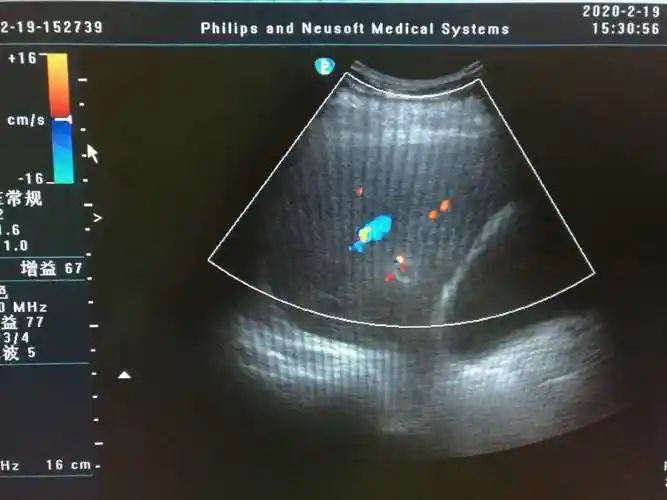

考虑急性坏疽性胆囊炎伴穿孔可能——zengerya - 超声医学讨论版

诊断 坏疽性胆囊炎伴穿孔 病例要点 超声上,复杂性或坏疽性胆囊炎可能

【请教】胆囊息肉有血流吗? - 超声医学 -丁香园论坛

气肿性胆囊炎超声表现为胆壁非游离面或腔内出现强回声(气体), 伴有